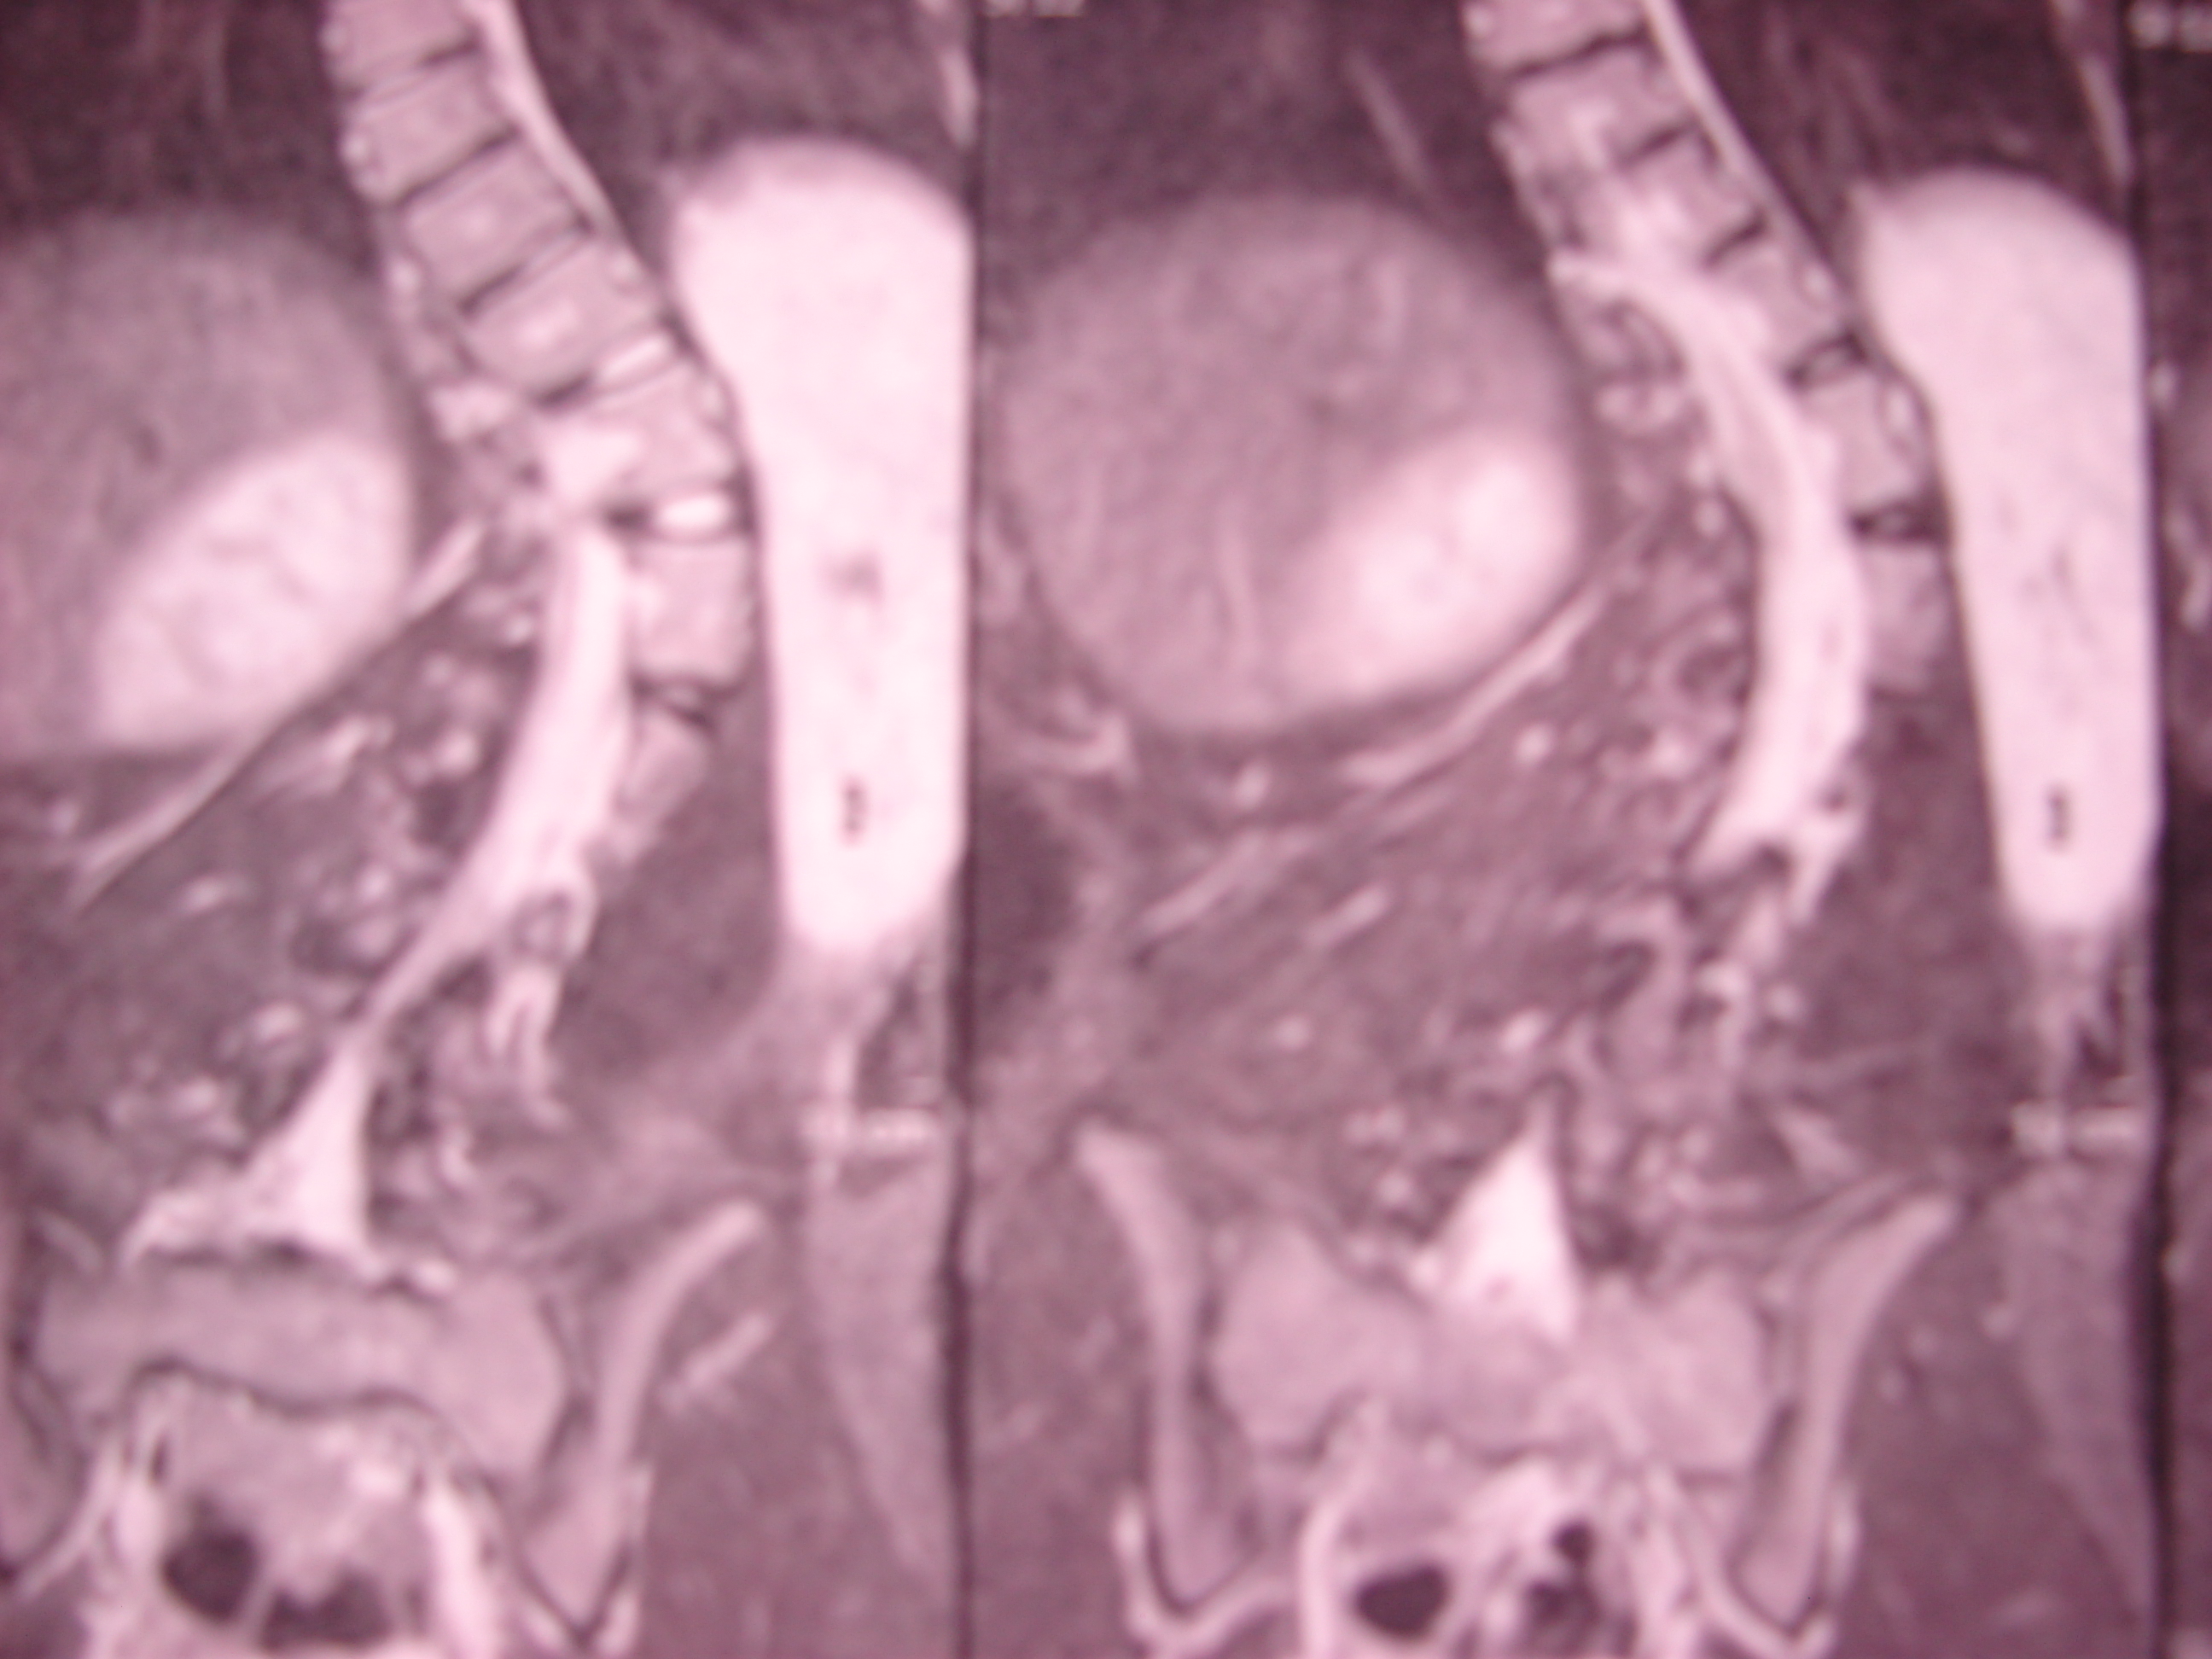

Εικόνα 2 α,β,γ,δ,ε

Οι ακτινογραφίες της σπονδυλικής στήλης δείχνουν την προοδευτική επιδείνωση της σκολιώσεως απο την των 15 ετών μέχρι των 18. Η σκολίωση είναι αριστερή θωρακοσφυϊκή (Θ10-ο3). Στην ηλικία των 15 ετών ήταν 30 μοίρες και στην ηλκία των 18 ήταν 86 μοίρες .